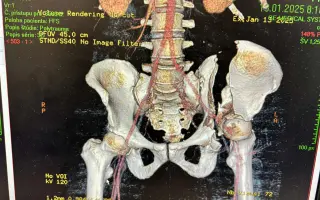

Volám sa Peter a 13. januára 2025 sa mi úplne zmenil život. Cestou pešo do práce ma zrazilo menšie nákladné auto z Česka. V priebehu sekundy som sa stal práceneschopným, pacientom s ťažkou polytraumou a trvalými následkami, lebo mi náraz zlomil panvu. Po nehode som bol hospitalizovaný takmer dva mesiace. Podstúpil som štyri operácie panvy a acetabula, ošetrenie poškodených nervov a dlhú pooperačnú rekonvalescenciu ktorú som ukončil koncom októbra 2025. Napriek všetkej liečbe mi zostali vážne zdravotné a psychické následky, ktoré ma významne obmedzujú v každodennom živote:

• Zlomenina acetabula (jamka bedrového kĺbu) – po opakovaných operačných stabilizáciách

• Zlomenina panvy – komplikovaná, s nutnosťou viacerých operácií

Pozrite si video zlomeniny mojej panvy, ktoré bolo urobené po nehode v nemocnici kde som bol hospitalizovaný.